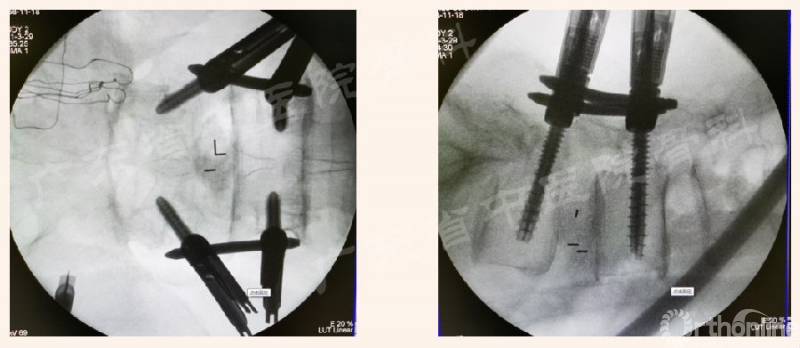

为进一步解决临床实际问题,本期内容将针对腰椎Endo-PTLIF的标准化流程,按照手术常规步骤中椎管外、进入椎管、椎管内的操作进行介绍,详见下文。

2. 椎板切除术

进入椎管的相关操作

椎管内的相关操作